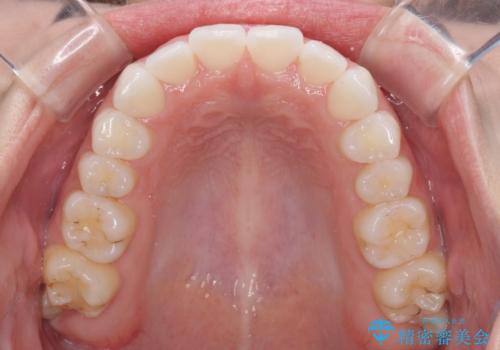

- 海外留学を前に上下のデコボコと奥歯の咬み合わせを改善したいとのことで来院された患者様です。

期間が限られていたため、ワイヤー装置による矯正治療を行うこととしました。

治療開始から4ヶ月ほどで概ね歯列が整い、その後の3ヶ月で細かい部分を仕上げていきました。

短期間で綺麗に仕上がり、患者様には大変満足していただきました。